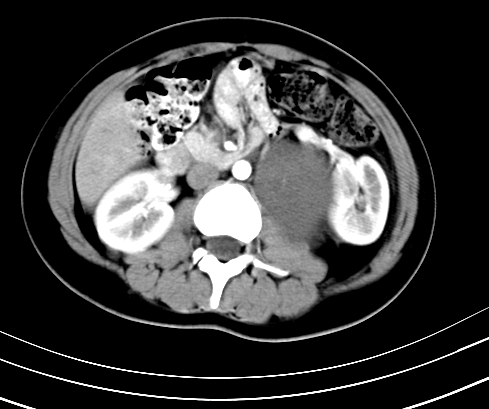

腹部平扫